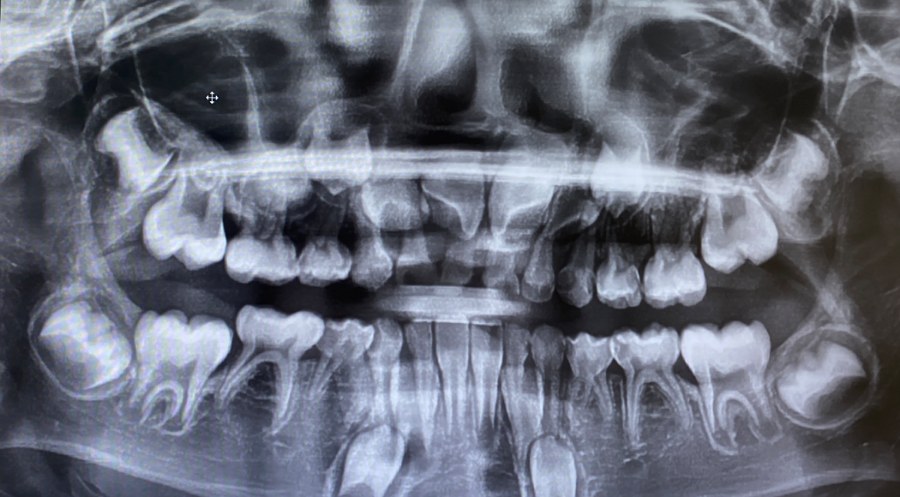

보통은 한두 개가 없는 경우가 많지만, 드물게 다섯 개 이상 결손되기도 합니다. 치과 검진에서 엑스레이로 확인하면 영구치 씨앗이 없는 걸 쉽게 알 수 있습니다.

영구치 결손은 특정 위치에서 잘 나타나는 경향이 있습니다.

▪️위 앞니 옆(측절치)

▪️아래 작은 어금니(소구치)

이 부위에서 결손이 가장 많이 보고됩니다. 위아래 합쳐 여러 개가 없는 경우, 치열 전체 균형에도 큰 영향을 줍니다.